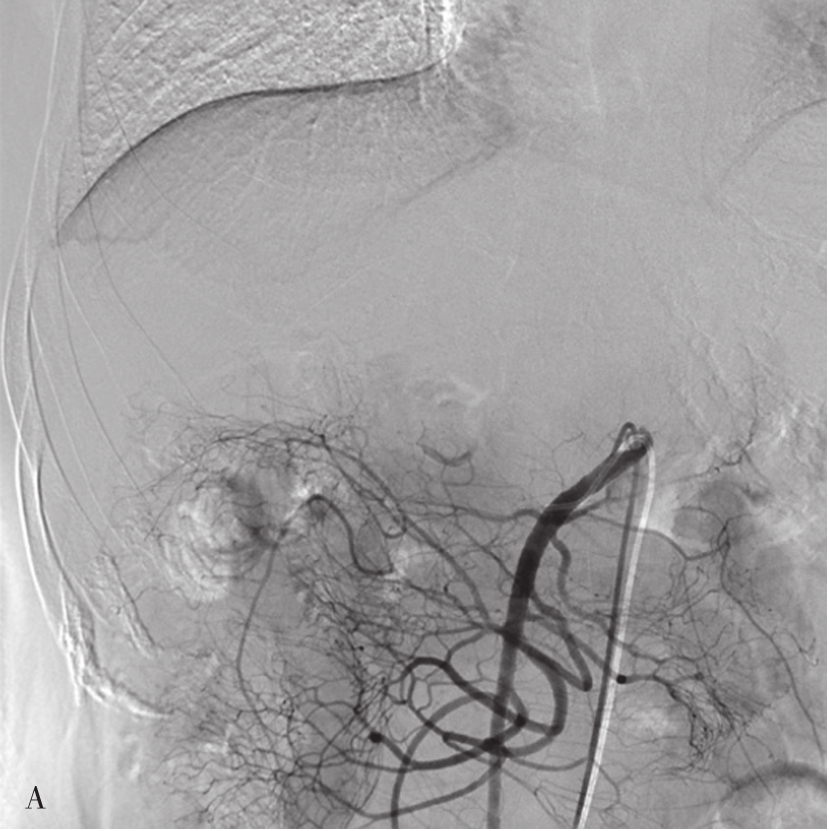

采用Seldinger技术穿刺股动脉成功后,插管入肝总动脉,行动脉造影,常规采用非离子碘对比剂,以6~8mL/s,总量20~30mL的速率注入,并连续摄片12秒以上,以观察肝总动脉及其分支,动脉供养器官的实质期和静脉回流的情况(图5-21-49)。如需要进一步观察肝脏的情况,可以超选择插管进入肝固有动脉或者肝左、右动脉。如经股动脉插管不成功,亦可选择经肱动脉和桡动脉等上入路。显示肝动脉和肝实质及回流静脉的情况,可有:①常规X线摄片检查,已被数字减影血管造影(digital subtraction angiography,DSA)取代;② DSA,是应用计算机辅助成像。动脉插管成功后,注入造影剂之前,首先进行第一次成像,并用计算机将图像转换成数字信号储存起来。注入造影剂后,再次成像并转换成数字信号。两次数字相减,消除相同的信号,得知一个只有造影剂的血管图像。这种图像可以更清晰和直观显示血管结构。显示血管的情况,除插管进入动脉后注入对比剂外,亦可经静脉注入对比剂后,根据对比剂的循环时间观察其显示的相应的血管。如CT动脉造影(CT angiography,CTA),将CT增强技术与薄层、大范围、快速扫描技术相结合,通过合理的后处理,清晰显示全身各部位血管细节,具有无创和操作简便的特点,对于血管变异、血管疾病以及显示病变和血管关系有重要价值。

图5-21-49 经股动脉穿刺行肝总动脉造影

A.可观察肝总动脉及其分支,动脉期可见肝右下富血供性占位病变(白色箭头);B.静脉期可见脾静脉和门脉干及其分支显示

本节主要介绍的是临床上常用的DSA。其适应证主要是:①观察肝脏动脉和门静脉等血管的病变和解剖变异,如血管畸形、动静脉瘘、血管狭窄或动脉瘤。②为肝脏占位性病变的位置和性质的诊断提供影像学证据(图5-21-50)。对富血供的病变,有可能发现直径小于5mm的病灶。③为经肝动脉的治疗建立了途径。如肝肿瘤的化疗栓塞、出血动脉的栓塞等。其禁忌证是相对的,主要是出凝血功能严重障碍和肾功能衰竭。肝动脉造影虽然是有创的检查,但其严重并发症的发生率低于1%。主要与动脉穿刺插管、对比剂的应用等相关。

图5-21-50 肝动脉造影

显示肝癌并门脉右支及主干癌栓,动脉期可见供养静脉癌栓的数条并行细小动脉(条纹征),为癌栓的供养动脉。RHA:肝右动脉;GDA:胃十二指肠动脉;SA:脾动脉。